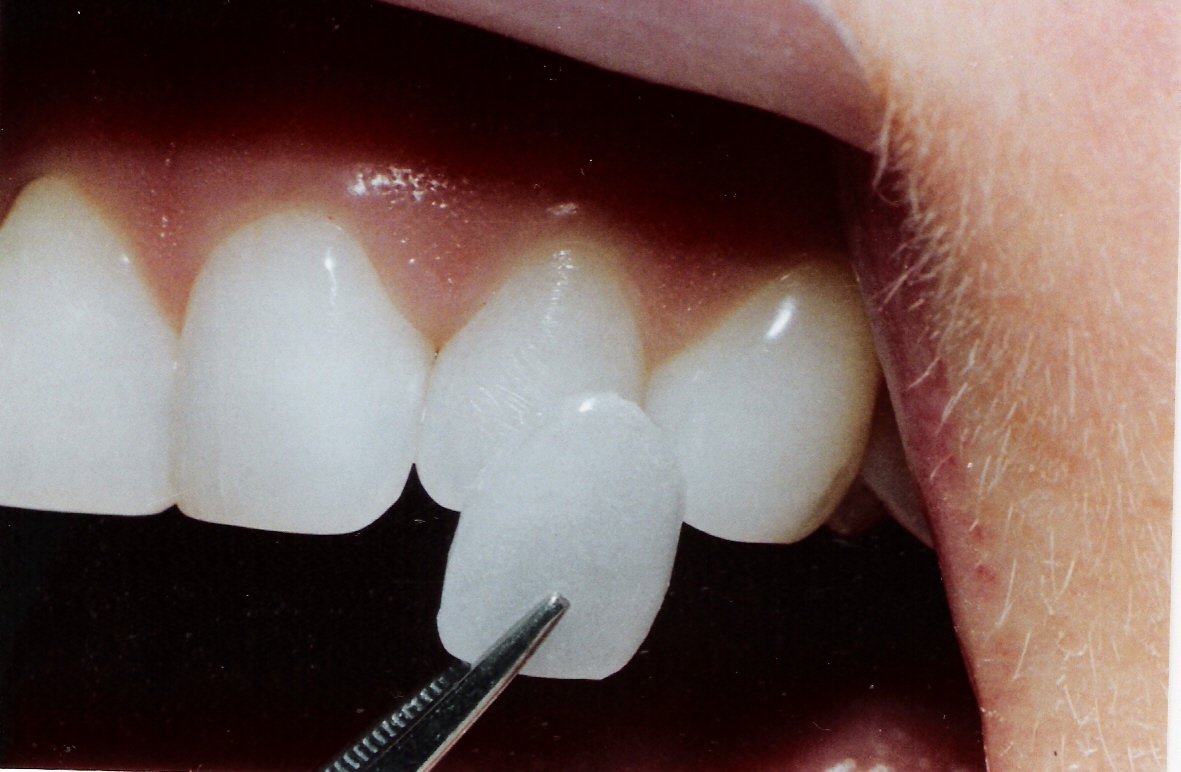

Veneers commonly called porcelain veneers and dental porcelain laminates, are thin layers of porcelain or resin composite restorative materials placed on the surface of a tooth to improve its appearance. This dental procedure is best used on patients with chipped, stained, worn and misaligned teeth. The great thing about having veneers is that they are highly resistant to staining and may last up to a decade. Getting dental veneers

requires three trips to the dentist, with the first visit for initial consultation, the second and third for making and applying the veneers.